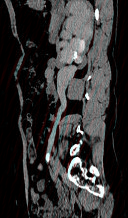

- 多项选择题患者女,44岁, 突发性胁腹部绞痛并向会阴部放射伴血尿一次。如图所示,以下说法正确的是 ( )

A、左肾输尿管未见异常

B、右输尿管内可见沿输尿管走行的高密度影

C、右侧肾盂肾盏扩张

D、右输尿管中上段扩张

E、右输尿管结石